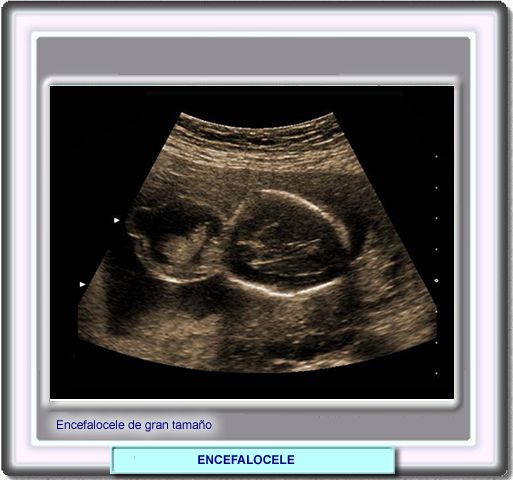

Cuando la ecografía detecta una masa extracraneal:

• cuando es quística probablemente es un meningocele.

• cuando es sólida con tejido cerebral puede ser un encefalocele o meningoencefalocele y

• cuando el ventrículo es encontrado en el saco del encefalocele esta presente un meningohidroencefalocele

Adicionalmente, la ecografía permite detectar otras lesiones como la ventriculomegalia (dilatación de los ventrículos) o defectos óseos en el cráneo (los pequeños defectos pueden no ser detectados).